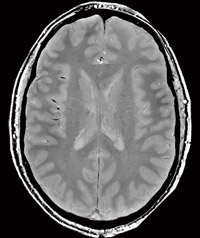

図4 7T用32チャンネル・ヘッドコイル(プロトタイプ)での初期画像

図4 7T用32チャンネル・ヘッドコイル

(プロトタイプ)での初期画像